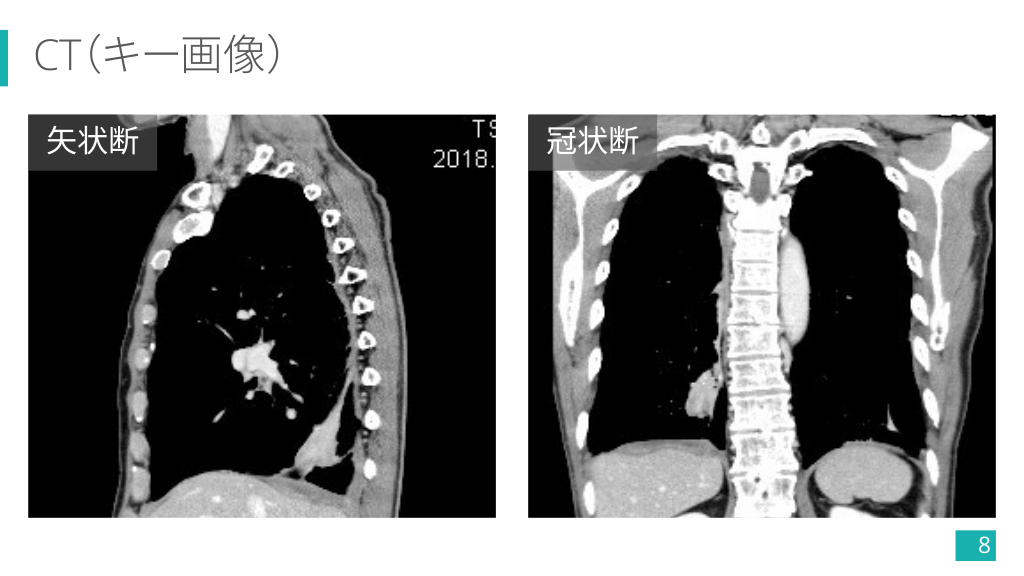

CT(キー画像) 矢状断 冠状断 8

CT(キー画像) 多発胸膜プラーク(一部石灰化+) 右肺下葉の卵円形腫瘤 14

CT(キー画像) 腫瘤へと曲線的に収束する気管支血管束 (comet tail sign) 15

CT, FDG-PET/CT 矢状断 肥厚胸膜から連続する腫瘤 FDG-PET/CT 淡いFDG集積(縦隔より弱い) 16

1-5) 円形無気肺の画像診断 Ø 肥厚した胸膜から連続し,胸膜と 鋭角をなす円形/卵円形腫瘤. Ø 腫瘤に向かい,気管支血管束が曲 線的に収束する像 (comet tail sign) が特徴的. Ø 造影効果は様々. 5) より引用 28

今回の症例で診断の流れを復習!! ① 胸膜プラークが多発してるし, アスベスト曝露ありそうだな〜. ② 右下肺野に腫瘤影あるな〜. ③ CTでも胸膜プラーク多発してる. ④ 右肺下葉の腫瘤は胸膜から連 続して comet tail sign もありそう. ⑤ FDG の集積も縦隔より弱い!! 円形無気肺でよさそう 34